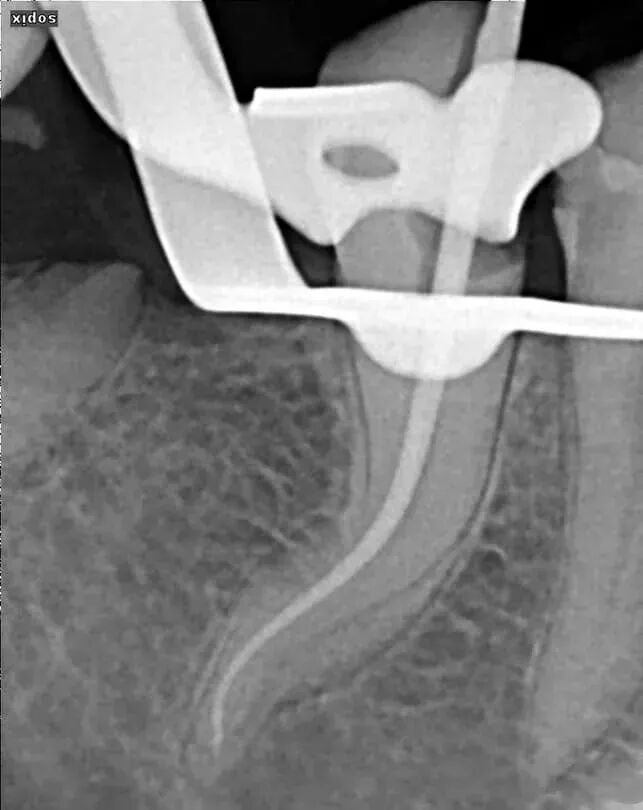

测定根管长度用以下三种方法结合:x片法、根测仪测量、手感法。建议首要以根测仪(COXO宇森医疗根测仪个人体验和进口的没什么区别,测量数据很准确,稳定性不错,支持国货)为准。

但是对于以下三种情况根测仪可能出现不准确,所以建议拍初挫片:

a、根尖孔破坏或根尖孔较大的患牙。

b、根尖暗影较大的患牙。

c、经过一次不彻底拔髓后有残髓的患牙。